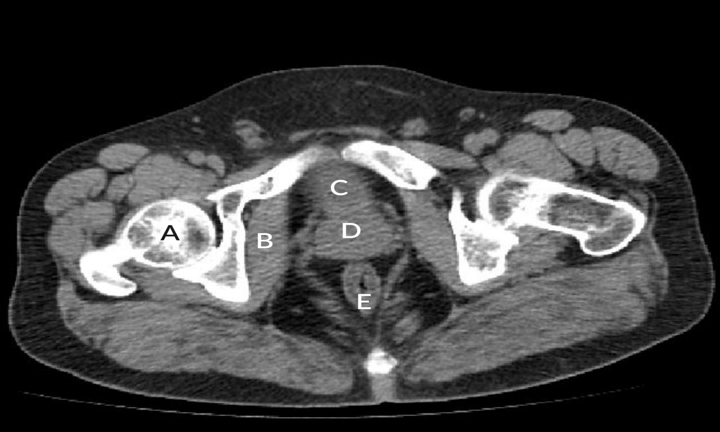

CT :

Poor for assessment of prostate zonal anatomy and pathology.

It is helpful in determining the extent of local spread as well as lymph node metastases.

Pelvic CT

(A) Right femoral head(B) Right obturator internus muscle(C) Urinary bladder(D) Prostate(E) Rectum